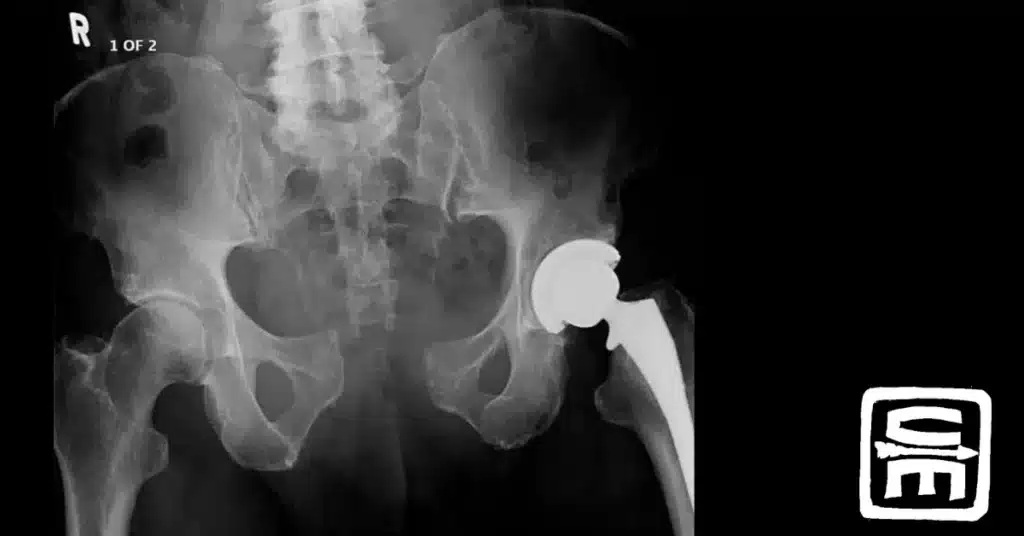

“Pelvic fractures are common in combat injuries and may be highly lethal. Twenty-six percent of service members who died during OIF and OEF had a pelvic fracture.” 1 This led to the TCCC committee adding pelvic binders to their guidelines …